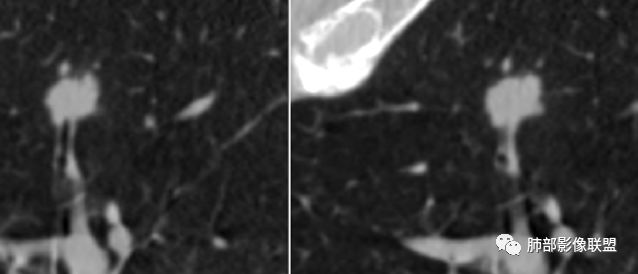

胸膜下结节,边界清楚、光滑,边缘稍凹陷,有胸膜牵拉

血管进入?

脐凹?

支气管在门口堵了

似有浅分叶

门口支气管堵塞——提示与支气管相关,不支持良性肿瘤

似乎有脐凹征

除了胸膜牵拉,还有短毛刺?血管纠集

支气管在门口堵塞

病例1为胸膜下实性小结节,血管脐凹样出入,可见支气管阻塞。病灶膨隆,部分边缘平直,周围晕征不明显,未见分叶,但可见毛刺及胸膜牵拉,增强后明显强化,老年男性,怀疑新生物尤其是腺癌是有理由的。